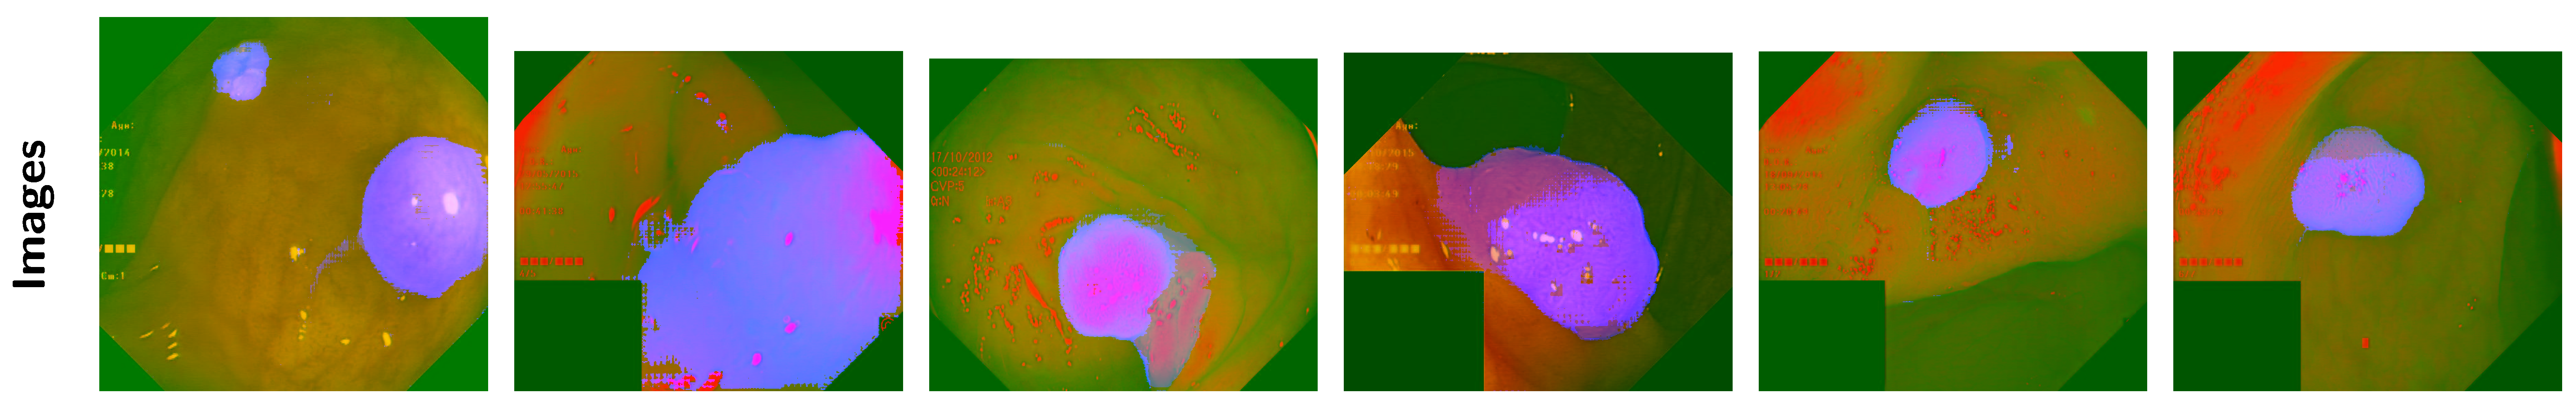

Appendix B. Channel Visual Comparison